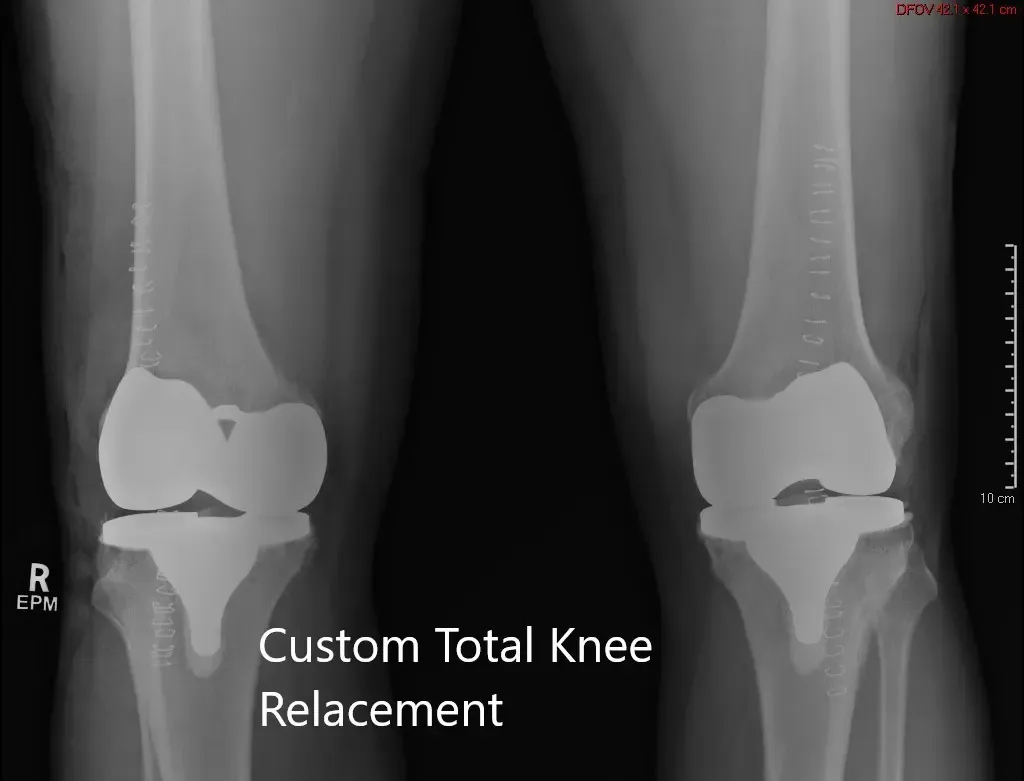

Postoperative X-ray showing the AP view of both knees.

Postoperative X-ray showing the lateral view of the right and the left knee

Post-op the patient was walking the same day of surgery with support. Thrombotic-event-deterrent (TED) stockings were advised to the patient along with aspirin for deep vein thrombosis prophylaxis. The patient’s pain was managed well with medications.

Sutures were removed the 14th-day post-op uneventfully. The patient reported zero pain at the two months follow up. She was walking without the support and had a full range of motion of both knees. She was extremely happy with the outcome. She follows up as needed.